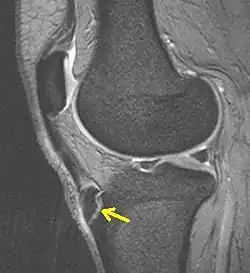

Eine Bildgebung kommt bei atypischer Symptomatik in Betracht, dann je nach Fragestellung und Differentialdiagnose Sonographie des Sehnenansatzes (DD:Bursitis, Abszess), eine Röntgenaufnahme seitlich oder selten eine Kernspintomographie. Diagnostische Kriterien sind dann Fragmentation der Tuberositas, Auftreibung der ansetzenden Sehne, Weichteilödem sowie im MRT angrenzende Ödeme in der Tibia.